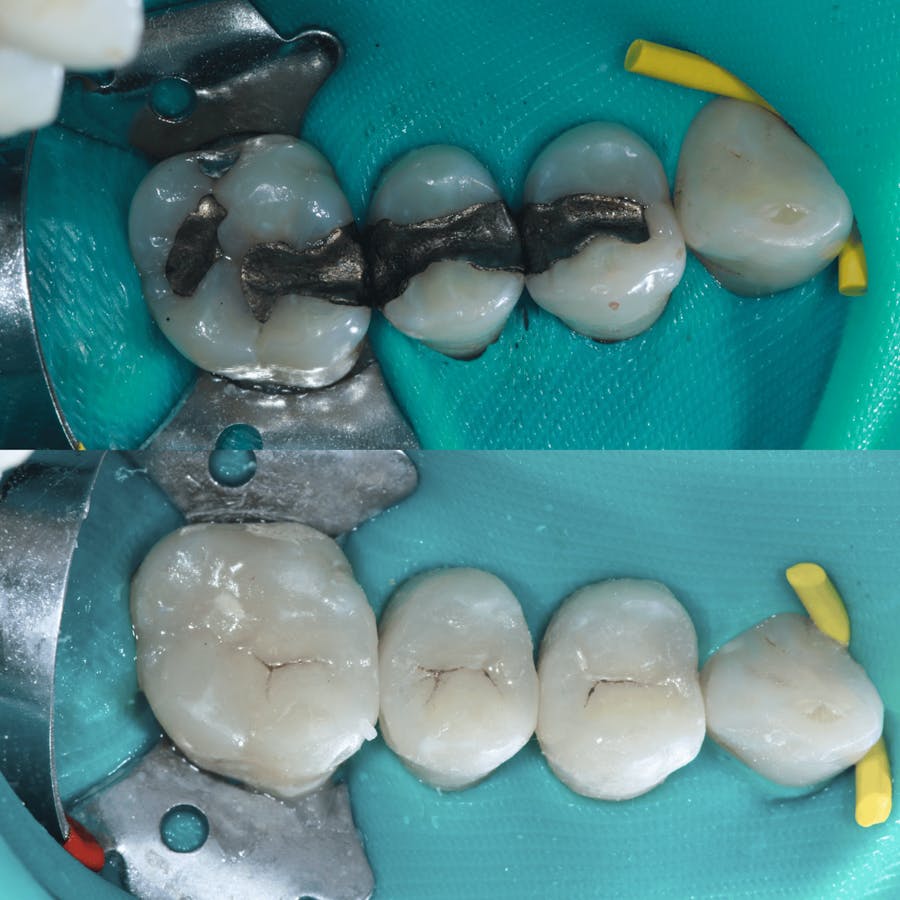

Dr. O’Malley’s holistic care is grounded in the science of biomimetic dentistry: a technique that restores teeth using materials and dental engineering principles to rebuild the teeth as close to mother nature as possible. This process allows him to rebuild strength and flexibility while preserving vitality. Every treatment begins with a comprehensive assessment that considers the relationship between your teeth, bite, gums, and overall wellness. Treatment plans are customized to protect long-term health and reduce the need for future intervention.